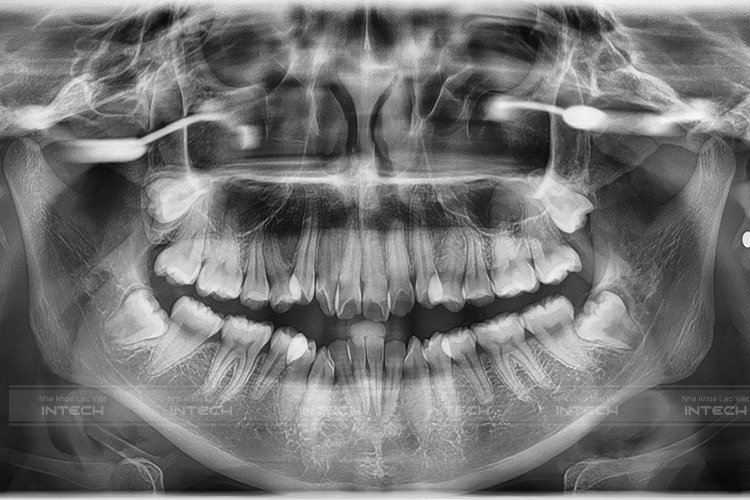

Kế quả chụp phim CT Conebeam của Quế Vy tại Lạc Việt Intech

Sau khi thăm khám, dựa trên các dữ liệu chụp phim và tình trạng ban đầu, đội ngũ chuyên gia tại Lạc Việt Intech đã lên phác đồ điều trị cụ thể nhất cho Quế Vy. Qua đó bạn sẽ được niềng răng bằng mắc cài kim loại kết hợp công nghệ X-Matrix.